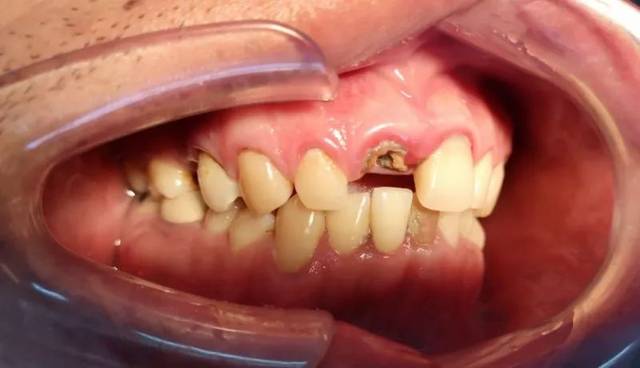

哪些牙齿疾病需要做根管治疗 在日常生活中,也可能因牙齿外面的硬组织受伤缺损,使牙神经也受损伤而引起坏死:牙神经一旦坏死,不但影响牙齿的功能,而且还会引起牙齿病变,所以人们通常将坏死的牙神经... 根管治疗 阙德厚 638 2024-01-24